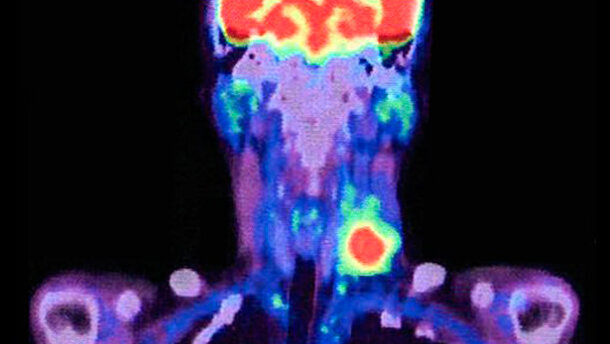

Houston, Columbus e Miami (Usa) ‒ Un team di ricercatori è stato in grado di identificare con precisione il linfonodo sentinella – il primo attraverso cui si diffonde un cancro – nel cancro a cellule squamose (HNSCC) della testa e del collo, utilizzando un nuovo tracciante radio. La scoperta rappresenta un significativo passo in avanti nel ridurre le complicanze causate dalla dissezione del collo in pazienti con tumori della testa e del collo.

I ricercatori statunitensi ora hanno scoperto che il Tilmanocept può individuare esattamente il linfonodo sentinella negli HNSCC, cosa difficile, poiché ne esistono fino a 150 di diversi nel collo. Con il nuovo tracciante, il numero di pazienti HNSCC attualmente sottoposti a dissezione selettiva del collo potrebbe ridursi significativamente.

Per testare l'efficacia del Tilmanocept applicato al cancro del collo e della testa, i ricercatori hanno effettuato un test con i pazienti affetti da HNSCC in fase iniziale, in 12 diversi centri medici negli Stati Uniti. Gli 83 candidati a subire la dissezione del collo, sono stati sottoposti al tracciante ed i ricercatori sono stati in grado di identificare e rimuovere il linfonodo sentinella in almeno 81 di essi.

Messo a confronto con ricerche che prevedono l’utilizzo di traccianti standard radio-colloide, l’impiego del Tilmanocept per la biopsia del nodo sentinella ha comportato un elevato tasso di identificazione dei nodi sentinella (e uno ridotto di falsi negativi) in tutti i siti della cavità orale, rendendo in tal modo assai più agevole la previsione di diffusione del cancro.